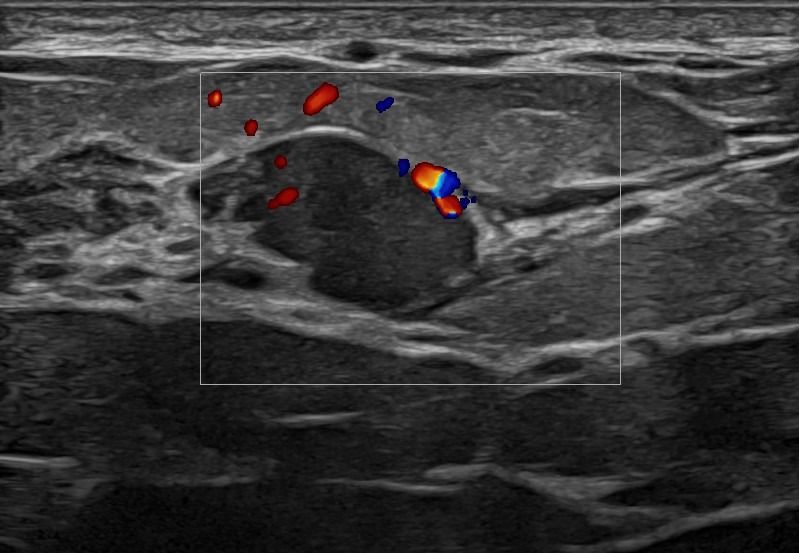

Modern ultrasound machines, equipped with advanced high-frequency transducers, techniques such as Color Doppler, Power Doppler, B-Flow, and Elastography, allow the analysis of breast architecture with exceptional accuracy.

Elastography can highlight the elasticity of a lesion, indicating whether it is hard or soft. Through this technique, we can assess the nature of the lesion, providing indications of whether it is benign or malignant. Additionally, with the contribution of Color Power Doppler and B-Flow, we can monitor the vascular flow within the lesions, offering even more information about the type and nature of the abnormality.